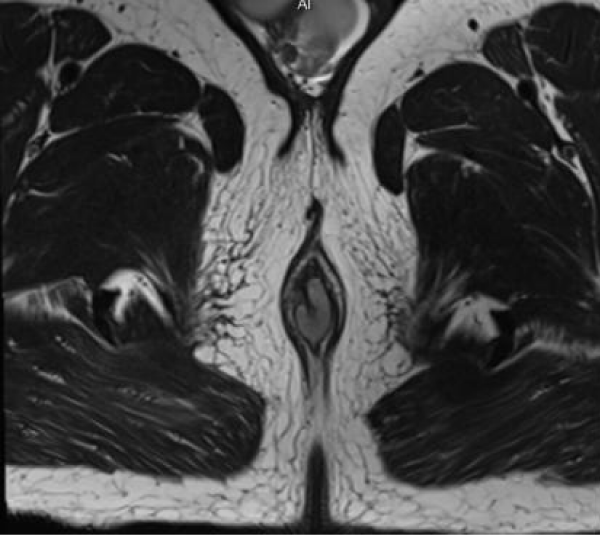

MR imaging revealed short segment circumferential wall thickening of the anal canal with lower margin approximately 1.7cm from anal verge. It was nearly 3 cm in length and 7mm in maximum thickness. The wall thickening showed hyperintense signal in T1-weighted images and T2-weighted images (Figures 1-3). Restricted diffusion with corresponding low signal in ADC map was noted figure 4. Post gadolinium T1-weighted fat saturated images showed hyper enhancement of the wall thickening (Figure 5). The thickening was involving the internal sphincter. No invasion of intersphincteric plane and external sphincter was noted. No extension into perianal fat was noted. Few enlarged heterogenously enhancing lymph nodes were noted in right inguinal region largest 23 x 21 mm in size. The patient underwent wide local excision with right inguinal dissection and adjuvant loco-regional radiotherapy. The histopathological examination showed features suggestive of primary anal malignant melanoma (Figure 6). In routine follow up, the patient showed no features of local recurrence or distant metastasis.

Figure 2: Axial T2-weighted MR image also shows hyperintense signal of the wall thickening.